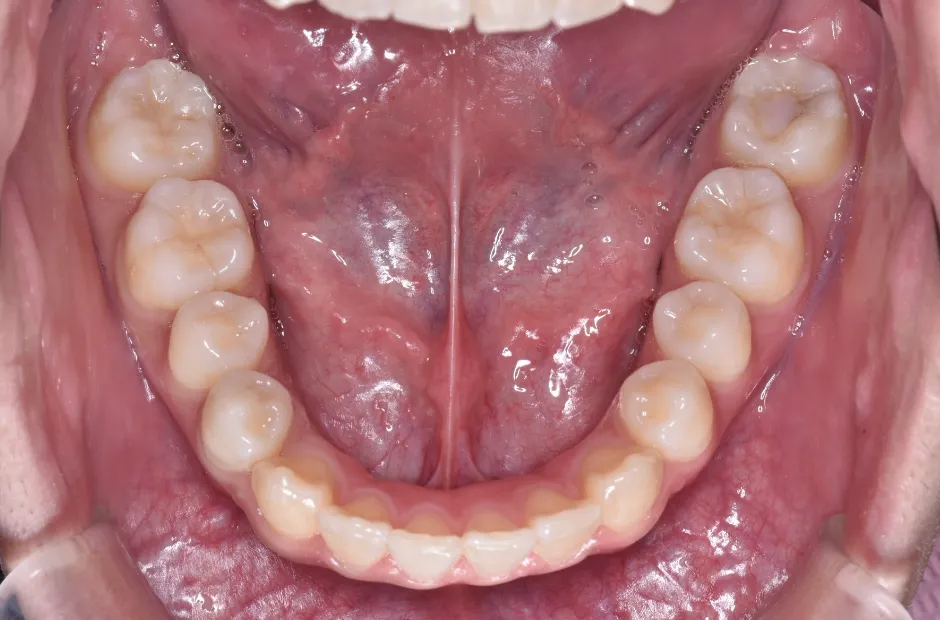

叢生

| 診断名・主訴 | 叢生 |

|---|---|

| 年齢・性別 | 43歳・女性 |

| 治療期間・回数 | 2年7か月 27回 |

| 治療に用いた主な装置 | 舌側矯正 |

| 抜歯部位 | 両顎4,4 |

| 治療費 | 100万円(税抜) |

| リスク・副作用 | 装置による違和感・疼痛・歯肉退縮・歯根吸収・虫歯のリスクなど |

治療前

治療後